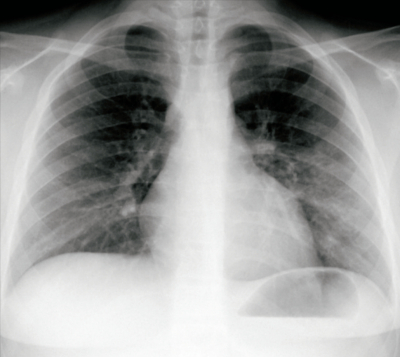

血液所見:赤血球 508万、Hb 14.3 g/dL、Ht 41 %、白血球 5,300(好中球 45 %、好酸球 2 %、好塩基球 1 %、単球 10 %、リンパ球 42 %)、血小板 30万。血液生化学所見:AST 22 U/L、ALT 24 U/L、LD 238 U/L(基準 120-245)。CRP 3.6 mg/dL。新型コロナウイルス〈SARS-CoV-2〉PCR検査は陰性であった。胸部エックス線写真及び肺野条件の胸部CTを別に示す。